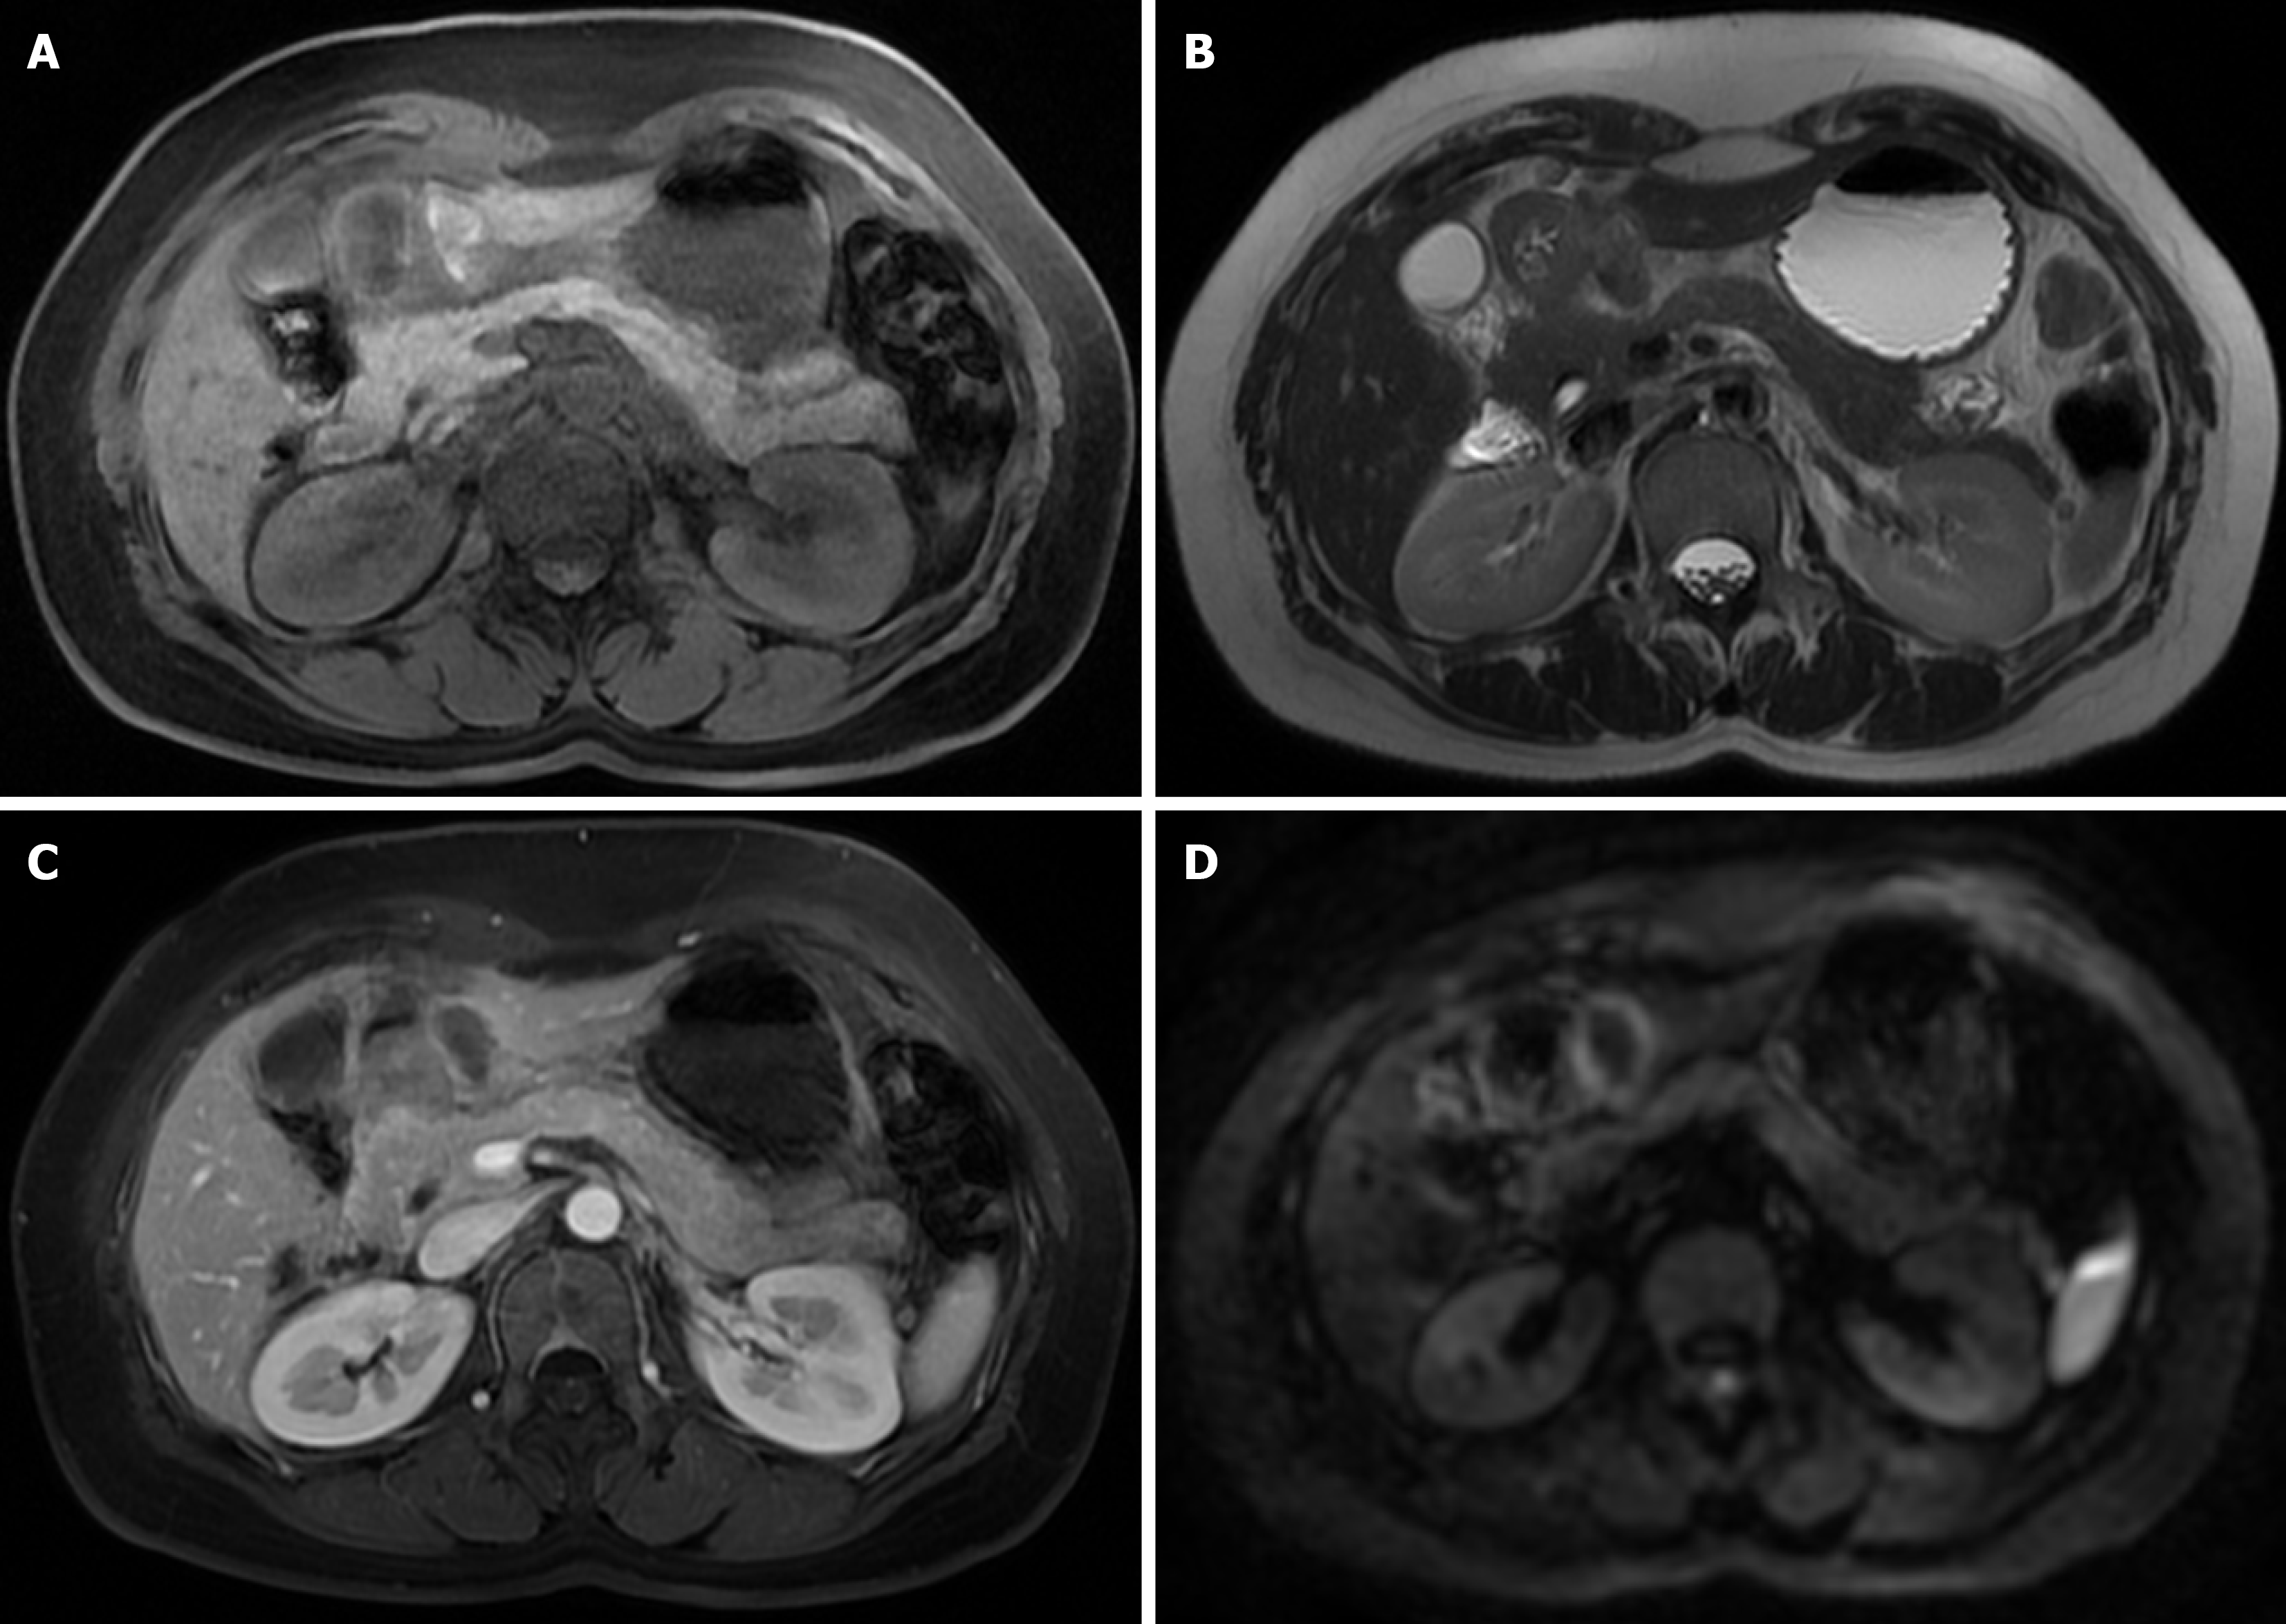

Contrast-enhanced abdominal CT demonstrated irregular thickening of the gastric antral wall with heterogeneous enhancement. A cystic lesion (3.4 cm × 2.2 cm) was found adjacent to the lesser curvature of the gastric antrum, exhibiting thick-walled morphology, blurred margins, and mild enhancement post-contrast (Figure 1). Two omental nodules near the inferior liver margin and enlarged lymph nodes in the hepatogastric ligament and mesentery were observed. MRI revealed an abnormal signal lesion (2.8 cm × 1.5 cm) lateral to the lesser curvature of the gastric antrum, showing hyperintensity on T1 weighted imaging (T1WI) (Figure 2), hypointensity on T2 weighted imaging (T2WI) (Figure 2), and no enhancement post-contrast (Figure 2). The vertical-axis ultrasound gastroscopy scan shows a uniform echo in the gastric body. A low-echo mass-like change approximately 3.0 cm × 2.2 cm in size is observed on the outer wall of the gastric antrum (Figure 3), with uneven internal echoes and visible high-echo structures (Figure 3). Based on the imaging findings, a hematoma or inflammatory lesion was suspected, with malignancy not excluded.

Usually, AA lesions are discovered through imaging examinations after consultation, so it is particularly important to identify AA during imaging. In the past, scholars have studied the manifestations of AA on CT, MRI, and B-ultrasound. Five female patients with AA underwent CT and MRI studies, which showed a well-defined mass that displaced adjacent structures. The tumor had low attenuation relative to muscle on CT. On MRI, the tumor was isointense relative to muscle on T1WI, hyperintense on T2WI, and enhanced after gadolinium contrast with a characteristic “whorl” internal pattern. MRI demonstrated the extent of the tumor and its relationship to the pelvic floor. The appearance of recurrent tumors was similar to that of the primary lesion[19].

On MRI, AA is hypodense relative to muscle and appears layered or swirling after contrast injection. AA is isointense relative to muscle on T1WI and hyperintense on T2WI, which is enhanced after gadolinium injection, indicating rich blood vessels. The tumor fibrovascular stroma is enhanced, showing a characteristic layered or swirling appearance[20].

AA may be identified on enhanced CT or MRI due to the characteristic internal structural features on contrast-enhanced CT or T1-weighted MRI, namely “swirling”, and the low-signal band structure of fibrovascular tissue can also be shown on T2WI. However, compared with CT, MRI can show the margins of the tumor relative to the surrounding structures, especially the dynamic contrast-enhanced sequence, so it is more helpful for preoperative assessment of the scope of surgery[21].

In this case, AA grew outside the gastric wall, and no characteristic “whirlpool” pattern was seen on CT and MRI. In addition, AA showed cystic lesions on CT, without the characteristic whirlpool sign of AA in the perineum. Therefore, we speculate that the previous typical AA imaging findings cannot be used for AA in rare sites such as the gastric wall.